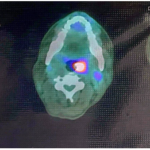

Case lâm sàng: Điều trị miễn dịch kết hợp thuốc kháng tăng sinh mạch cho bệnh nhân ung thư biểu mô tế bào gan tại trung tâm y học hạt nhân và ung bướu – BV Bạch Mai

Case lâm sàng: Điều trị miễn dịch kết hợp thuốc kháng tăng sinh mạch cho bệnh nhân ung thư biểu...